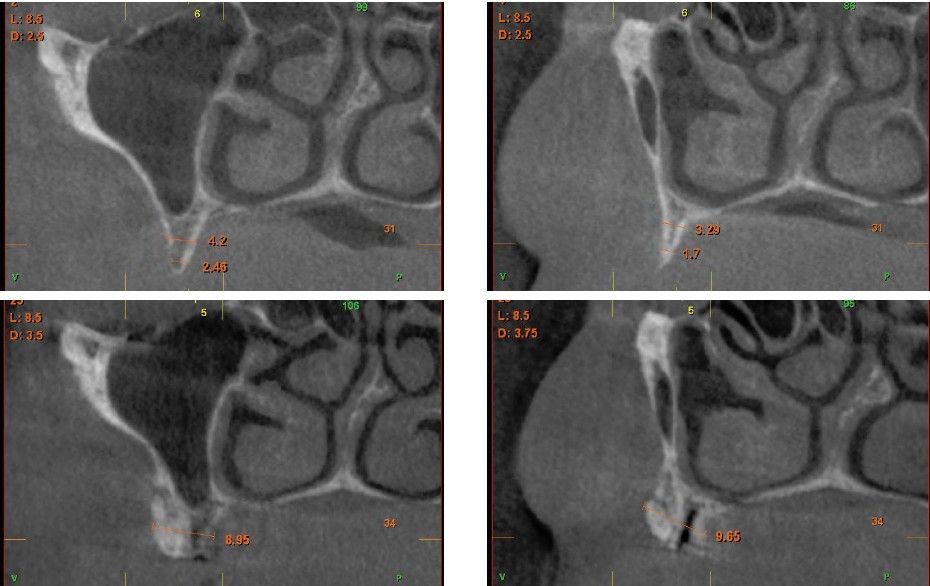

Fueron reclutados pacientes de forma retrospectiva con atrofia ósea horizontal severa (con anchura residual de cresta menor o igual a 3 mm), donde se colocasen injertos en bloque para regeneración ósea y posteriormente se insertarán implantes, con un tiempo de seguimiento tras la carga mayor o igual a 10 años. Antes de la colocación de los implantes, todos los pacientes fueron sometidos a una evaluación integral que incluyó modelos diagnósticos, un examen clínico intraoral detallado y un estudio tomográfico mediante Cone beam (TAC dental). Las imágenes obtenidas fueron analizadas con un software especializado (BTI-Scan III) para garantizar una planificación tridimensional precisa. Posteriormente, se llevó a cabo un encerado diagnóstico que sirvió como base para la creación de una guía quirúrgica, optimizando la ejecución de la rehabilitación planificada. La posición final de los dientes obtenida del encerado será la que guíe el proceso de regeneración para lograr el volumen óseo necesario para colocar los implantes en la posición necesaria. Antes de la inserción de los implantes se utilizó una pre-medicación antibiótica consistente en amoxicilina 2gr vía oral una hora antes de la intervención y paracetamol 1 gramo vía oral (como analgésico). Posteriormente los pacientes prosiguieron con un tratamiento de amoxicilina 500-750 mg vía oral cada 8 horas (según peso) durante 5 días. Todos los injertos se obtuvieron de rama mandibular y fueron divididos en cortical y esponjosa, según la técnica de Khoury18. Se conservaron en PRGF-Endoret hasta el momento de su uso y el hueso particulado obtenido de la parte medular del injerto se colocó embebido en PRGF-Endoret fracción 2 sin activar. Una vez posicionados los injertos fueron fijados mediante material de ostesíntesis (KTOÒ– Biotechnology institute) y toda la zona intervenida se cubre con membranas de fibrina autóloga (PRGF-Endoret fracción 1 activada y retraída) antes de la sutura con monofilamento de 5/0 para lograr cierre primario. Los injertos maduran 4-5 meses y posteriormente se realiza un nuevo Cone beam para conocer la anchura lograda y planificar la inserción de los implantes. La inserción de los implantes fue realizada por un mismo cirujano, mediante la técnica de fresado biológico, a bajas revoluciones, sin irrigación26-28. Una vez transcurridos cuatro meses desde la inserción de los implantes, se lleva a cabo la carga de los mismos mediante una prótesis provisional de carga progresiva elaborada en resina, con estructura metálica de barras preformadas y atornillada a transepiteliales. Estas prótesis provisionales se mantienen de 3 a 6 meses, en función de la adaptación y requerimientos de cada paciente. Una vez transcurrido este tiempo se realizan las prótesis definitivas. Tras la colocación de las prótesis definitivas los pacientes entran en un programa de seguimiento al que acuden cada 6 meses. En estas visitas se realizan radiografías panorámicas de control y periapiacales en la zona de inserción de los implantes. Las radiografías periapicales se llevan a cabo con posicionador, para generar imágenes reproducibles y los pacientes son colocados para la radiografía panorámica con posicionador fijo en glabela y mentón, mordedor para zona interincisal con eje de línea media, plano bipupilar y frackfort (marca láser) y con los pies sobre marcas trazadas en el suelo, con el propósito de que sean altamente reproducibles los resultados. Sobre estas radiografías se llevan a cabo las mediciones necesarias para comprobar la estabilidad y pérdida ósea crestal de los implantes. Una vez obtenida la radiografía en formato digital es calibrada mediante un software específico (ImageJ) a través de una longitud conocida como es el implante dental. Una vez introducimos la medida de calibración, el programa informático realiza un cálculo basado en esta medida para eliminar la magnificación, pudiendo realizar mediciones lineales exentas de este error. En la visita final de seguimiento (10 años) se lleva a cabo un nuevo cone-beam para estimar la anchura ósea final tras el período de carga de los implantes y valorar la potencial reabsorción del volumen óseo logrado con la técnica regenerativa del injerto en bloque. El paciente fue la unidad de medida para el análisis de la edad, sexo y la historia médica. La variable principal estudiada ha sido el mantenimiento del volumen óseo logrado con la técnica regenerativa tras 10 años de carga. Como variables secundarias se han estudiado la supervivencia de los implantes y la pérdida ósea mesial y distal. La supervivencia de los implantes se calculó mediante el método de Kaplan-Meier. Los datos fueron analizados con SPSS v15.0 para windows (SPSS Inc., Chicago, IL, USA). Fue realizado un test de shapiro-Wilk sobre los datos obtenidos para constatar la distribución normal de la muestra.

Una vez regenerado el lecho óseo con los injertos en bloque, se obtiene una media de anchura de 6,77 mm (+/- 0,91), lo que supone un incremento medio de 5,35 mm para cada caso. En la figura 2 se muestra la anchura inicial y final para cada zona donde posteriormente se insertarán los implantes.

La media de la pérdida ósea mesial de los implantes estudiados en el final del período de seguimiento a los 10 años fue de 0,94mm (+/- 0,28) mientras que la media de la pérdida ósea distal fue de 0,77 mm (+/- 0,17). Durante el tiempo de seguimiento no se registró ningún fracaso en los implantes estudiados. La media de la anchura ósea a los 10 años fue de 6,26 mm (+/- 1,08). En la figura 4 se observa la diferencia entre la anchura inicial, la lograda tras la consolidación del injerto y tras los 10 años de seguimiento. En las figuras 5-19 se muestra uno de los casos incluidos en el estudio.